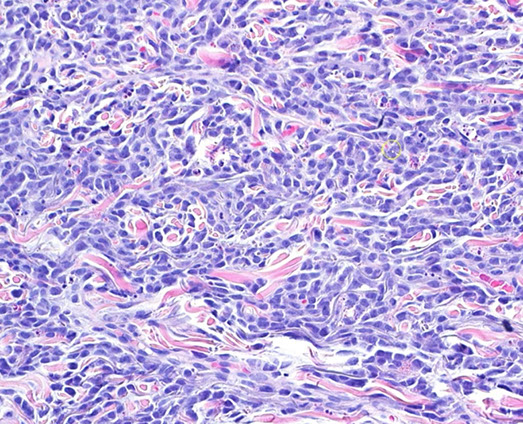

LyP type A

Lymphomatoid papulosis (LyP)

- a CD30-positive lymphophroliferative disorder

Rare, Indolent (self-healing) and chronic papulonodular skin dz c recurrent crops of pruritic papules at different stages of development that arises on the trunk and limbs; ~50 yo M, younger F

- histologically is a CD30+ proliferation of atypical T cells (is part of primary cutaneous CD30+ lymphoproliferatice disorders that includes Primary Cutaenous Anaplastic Large Cell Lymphoma [PC-ALCL] and borderline CD30+ lesions) - has many histologic mimics

- inc freq of prior, coexisting or subsequent lymphoproliferative disorders, usually mycosis fungoides or Hodgkin lymphoma

6 major subtypes:

Type A (MC, ~3/4): Hodgkin-like large atypical cells with intermixed mixed inflam infiltrates (neuts, lymphs, eos, histiocytes)

Type B: MF-like cerebriform cells c predominant epodermotrophic infiltrate

Type C: ALCL-like c large atypical cells and few other inflam cells (distinction from ALCL primarily clinical)

Type D: CD8+ cytotoxic T cell lymphoma-like c pagetoid infiltrate of epidermotrophic small to med-sized atypical CD8+ and CD30+ cells

Type E: Angiocentric infiltrates of small to med pleomorphic cells

Lyp with 6p23.3 rearrangement: Biphasic c small to med cerebriform cells and large atypical cells; usually seen in older adults

Micro: wedge-shaped infiltrate of T cells

IHC: (+) CD30 (CD30+ cells may be aberrant T cells) ,CD3 / 4

- neg ALK, CD8, CD56 (rare +)

DDx: Some immunoblasts, reactive T-cells, can be CD30+, scabies and arthropod bites can have a lot of CD30+ cells too

- Primary cutaneous anaplastic large cell lymphoma (PC-ALCL) can have lots of large ugly cells, the only way you would be able to differentiate is from IRF4 and the clinical history (if waxes and wanes, may consider LyP)

Dx: TCR rearrangement in 2/5 to 5/5 [1]

Px: excellent; although at inc risk secondary or nodal lymphoma such as MF, PC-ALCL and Hodkin lymphoma (up to 1/5)

- not known why there is spontaneous regression, but may be due to simultaneous expression of CD30 and CD95 (Fas) ligand

LyP - Scattered large cells with scattered smaller cells and neutrophils (mixed inflammatory background) wiht eos

LyP

LyP type C with diffuse sheets of CD30+ cells